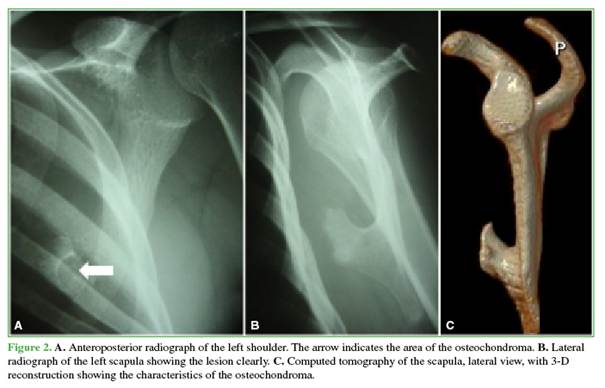

Complementary studies revealed a ventral osteochondroma near the inferior angle of the scapula (Figure 2). Computed tomography showed the typical mushroom-shaped image at approximately the level of the fifth rib and a homogeneous hypodense fluid collection measuring 16 × 5 cm. Traumatic bone lesions were ruled out. Ultrasound also demonstrated the fluid collection, measuring 150 x 30 x 80 mm (Figure 3).